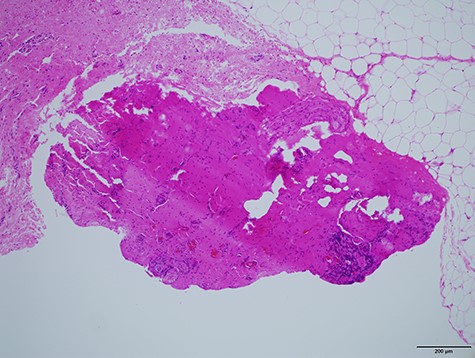

Histologically (Fig. 10), fibrosis and inflammatory granulation were seen. Inflammatory reaction of lymph nodes was observed. Epithelial cells could not be found in the slices.

Histological specimen of the final surgery. Inflammatory reaction of a lymph node inside of parotid the parotid gland was observed.